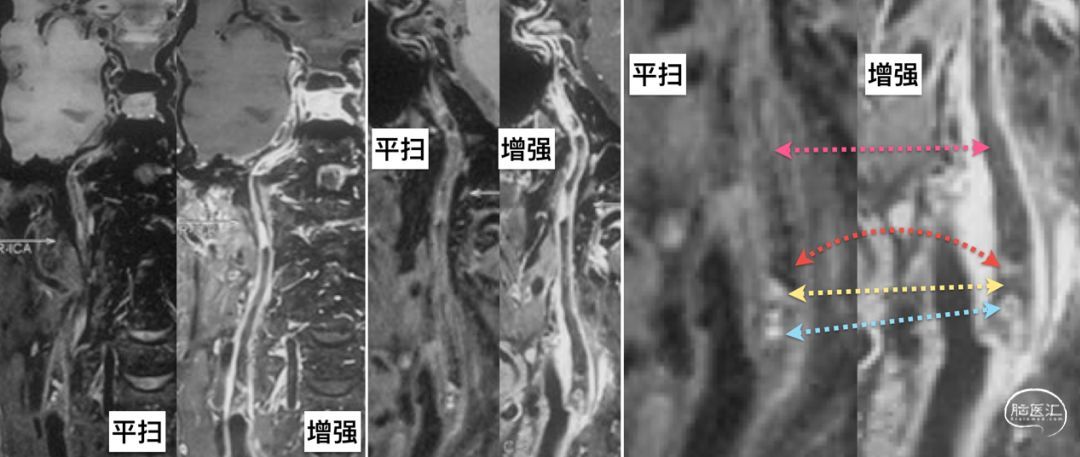

高分辨核磁显示ICA起始段是斑块组织,混杂信号,包括:

平扫低信号+增强高信号(下图红色箭头)

平扫高信号+增强低信号(下图黄色箭头)

平扫高信号+增强高信号(下图蓝色箭头)

感觉把几种组合都出现了一次![]() ;远端管腔则表现为平扫低信号+增强低信号(下图紫色)。

;远端管腔则表现为平扫低信号+增强低信号(下图紫色)。

我们又做了高分辨率核磁检查,给我们两个基本信息:

斑块位于ICA起始部,平扫高信号,但增强扫描显示斑块上段强化,下段信号降低;

ICA闭塞以远平扫高信号,并有明显的增强,这是什么斑块?到底闭塞了没有?

,在此也希望华扬主任的团队能够为全国的外科医生培养出更多“火眼金睛”。高分辨核磁对于术前的判断极为重要,几乎可以印证所有的斑块、血栓结构,能够很好地鉴别血栓的不同时期,对于慢血流也有独到的鉴别能力,平扫高信号+均匀强化的特征性信号。建议每位尝试做ICA慢性闭塞再通的医生,无论手术、介入还是复合手术,最好将HRMRI作为必选项。